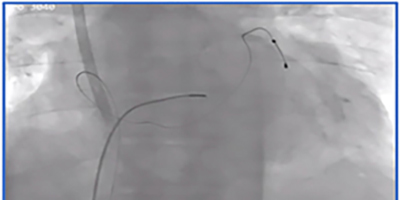

Coronary Sinus Stenting to Enable Left Ventricular Lead Implantation During Cardiac Resynchronization Therapy: A Case Report